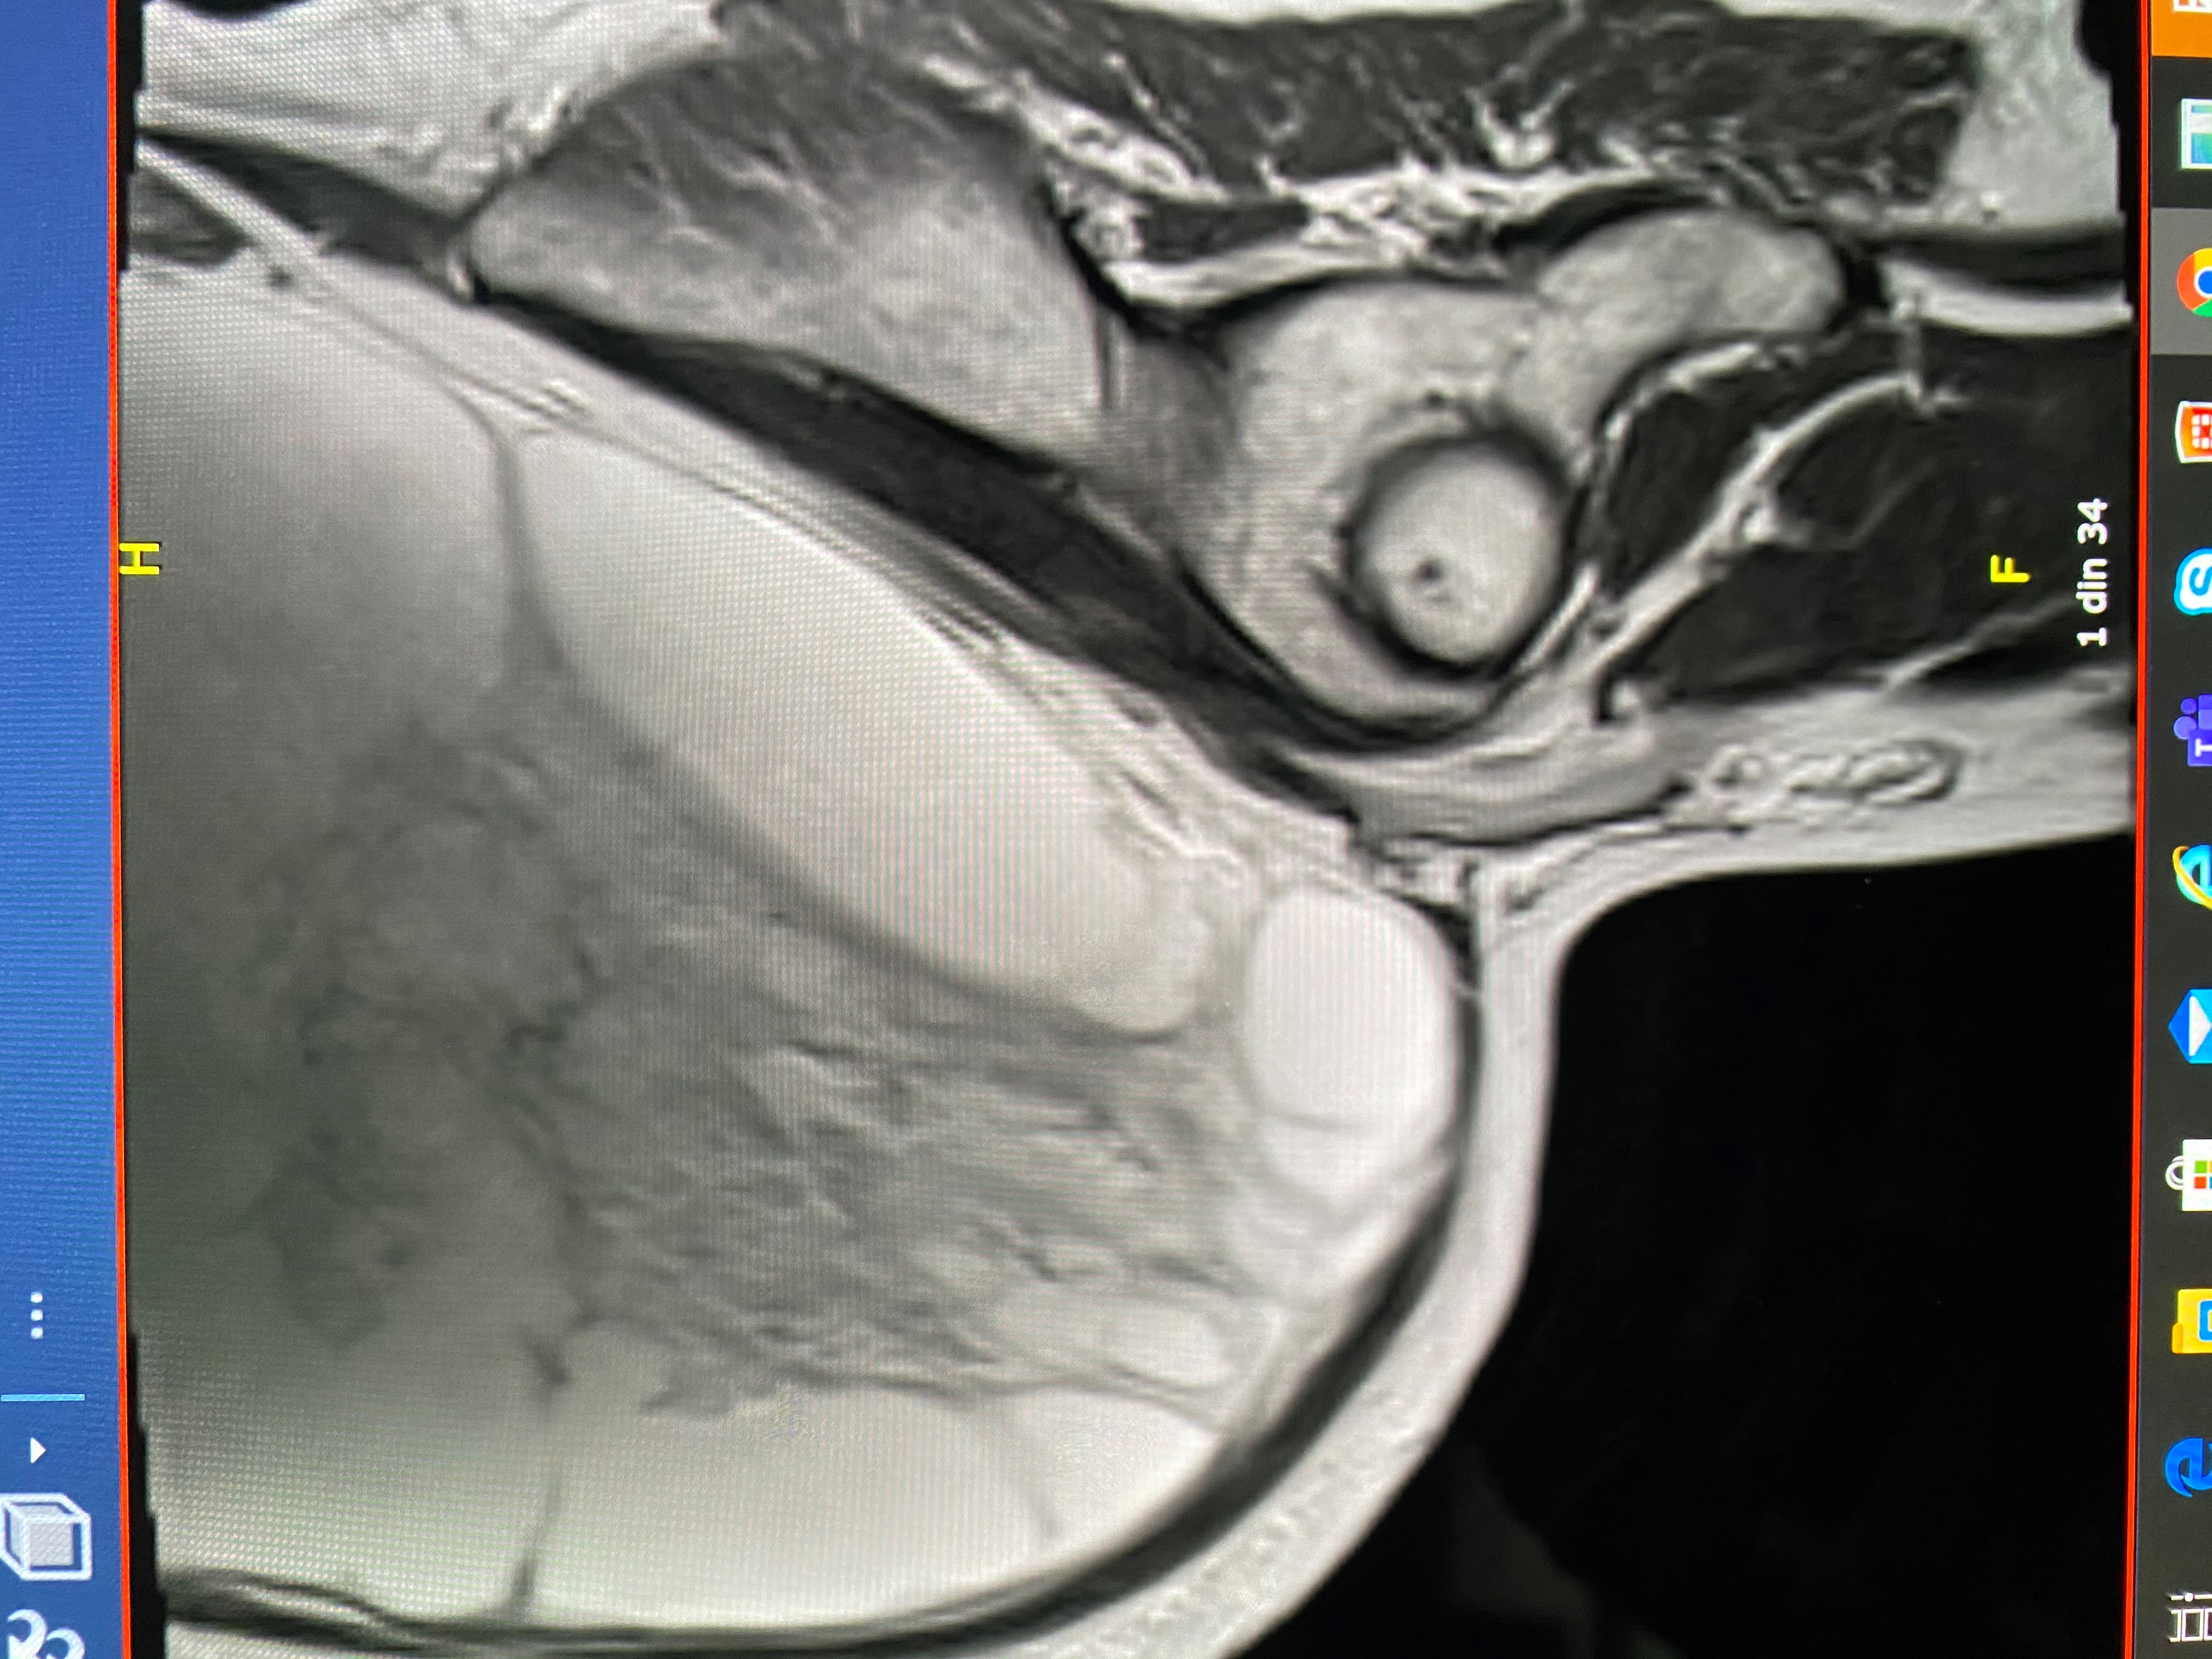

La examenul RMN se constata prezenta unei formatiuni tumorale abdominale chistice, de dimensiuni gigante. Avand un diametru orizontal de 33 de cm, tumora ocupa practic intreaga cavitate abdominala. Nu s-a putut stabili cu certitudine care a fost punctul de plecare si nici daca este vorba de o tumora benigna sau maligna.

Imagine RMN sectiune sagitala